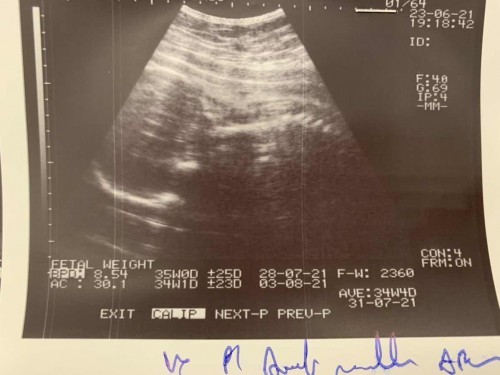

อายุครรภ์33+1แล้วค่ะ แต่เด็กยังไม่กลับหัว ผิดปกติมั้ยคะ กลัวได้ผ่าค่ะ ถ้าผ่า เบิกประกันสังคมได้หมดมั้ยคะ ขอบคุณค่ะ

ใจเย็นๆนะค่ะ บ้านนี้กลับหัวตอน 34+